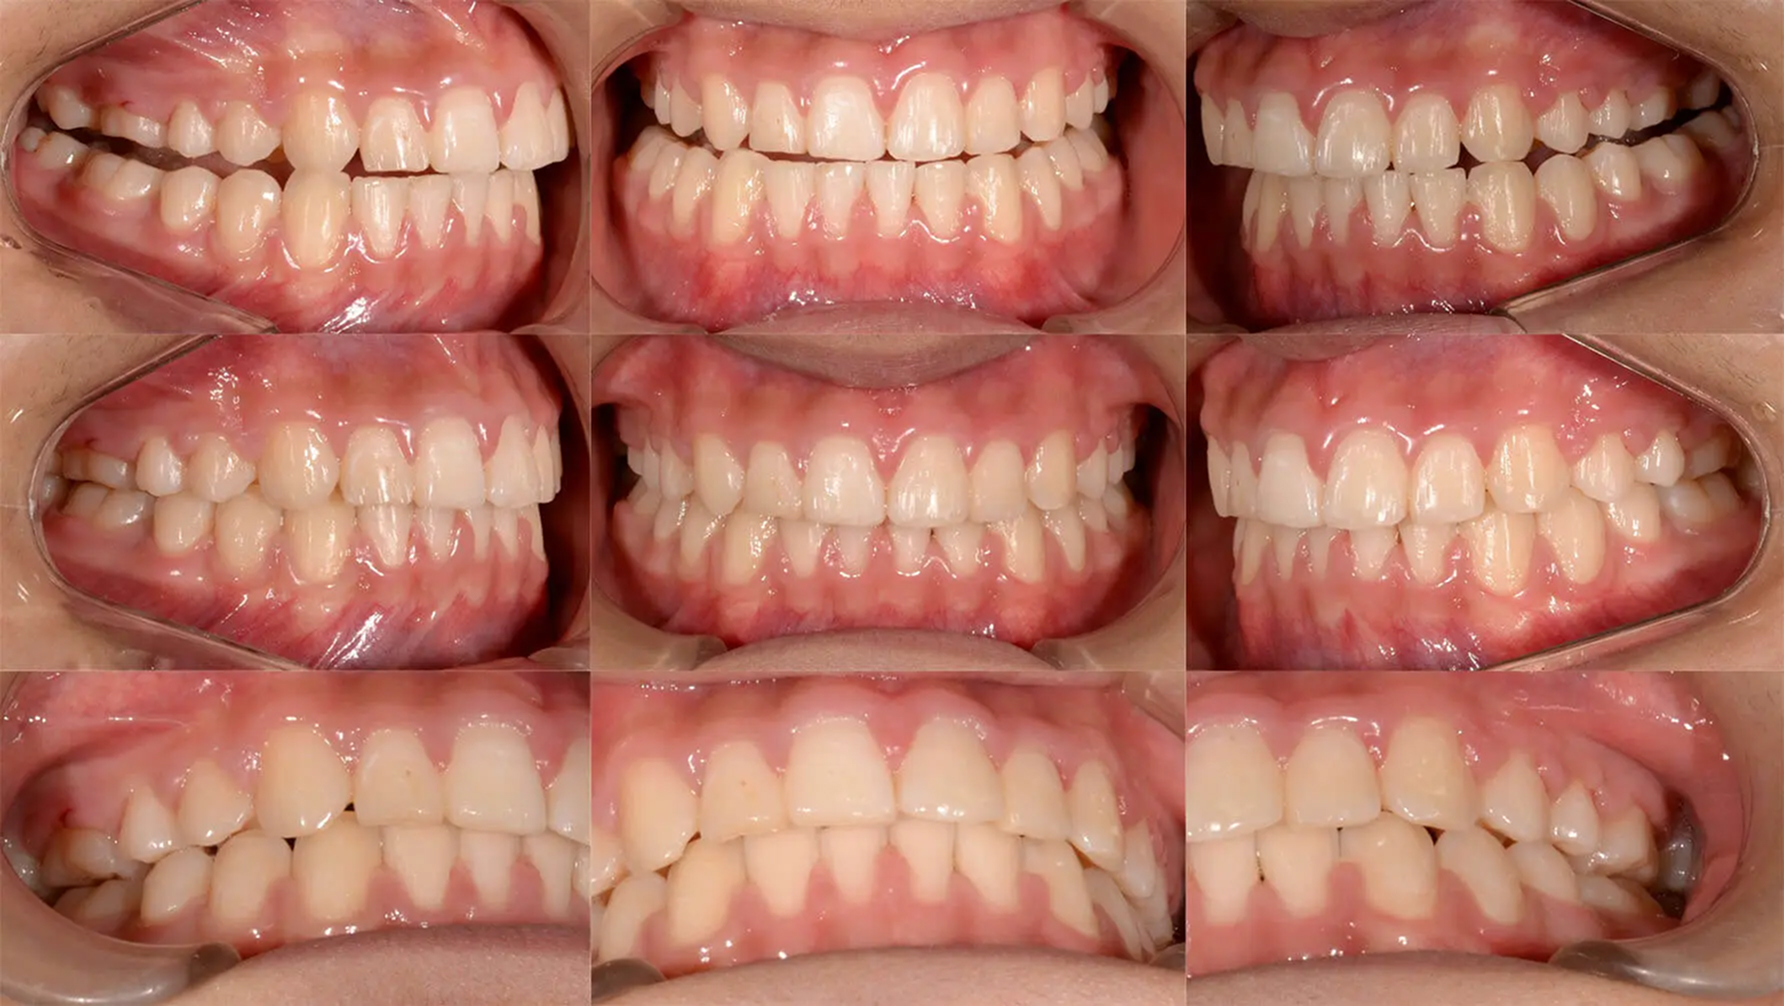

全体的な歯列不正が著しく、ブラッシングがしにくい状態でした。永久歯の異所萌出により両側上顎乳犬歯は晩期残存していました。診査の結果、歯列の狭窄を認めたため、オーバーレイアーチによる拡大を行えば、抜歯なしで矯正できると診断しました。かなり窮屈な部位もありましたが、きれいに歯列を整えました。むし歯治療も適正に行い、審美的な状態を獲得しました。

初診 2017.5.16

矯正治療開始 2017.8.7

ファイナル 2018.11.13

| 主訴 | 全体的な凸凹をきれいにしたい |

| 診断 | 両側アングル1級の叢生 |

| 矯正方法 | オーバーレイアーチを用いたマルチブラケット |

| 矯正期間 | 13か月・15回 |

| 費用 | 710,000円(税別) |

| 調整料 | 月1回 5,000円(税別) |